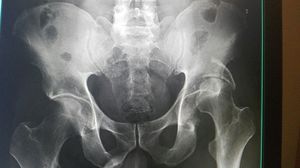

Xray

Fracture

Left

Acetabulum